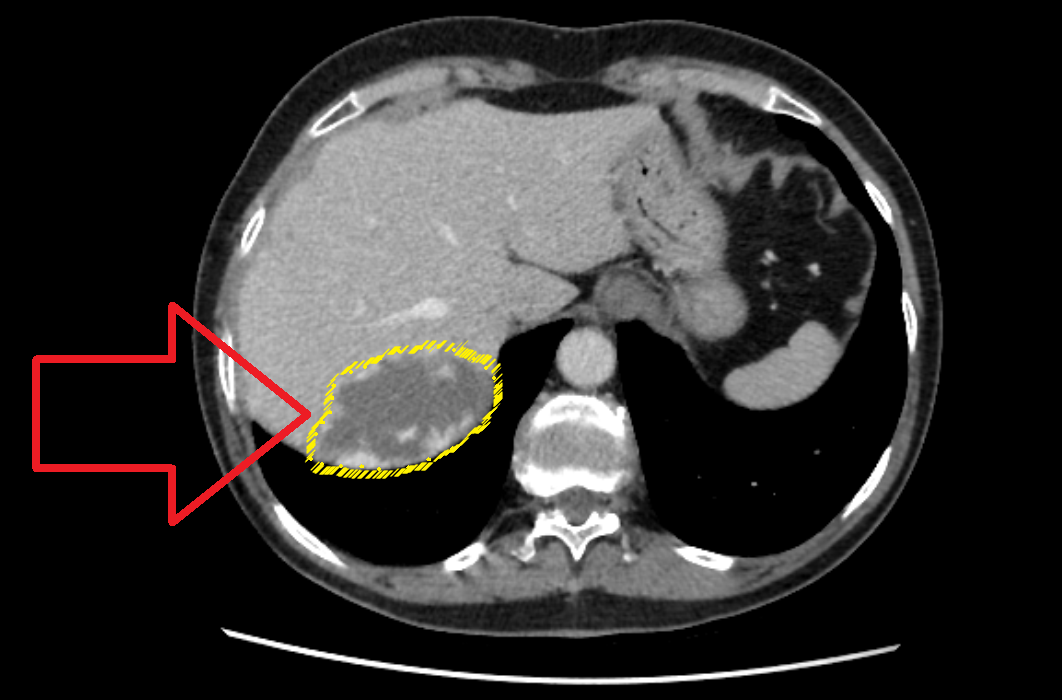

Белые точки на границе гемангиомы - зоны контрастирования.

В случае пациентки Е. по данным компьютерной томографии за 2022г. размеры гемангиомы были до 6,3 см в наибольшем измерении. В 2023 году гемангиома увеличилась уже практически до 7 см.

Размеры гемангиомы на данном срезе достигают 6,9 см в наибольшем измерении

Однако какие-либо клинические проявления гемангиомы у Е. отсутствуют, а лабораторные печеночные показатели идеальны.

Вывод: с учетом пограничных размеров гемангиомы, отсутствия каких-либо симптомов и нарушений функции печени, вопрос о хирургическом лечении в настоящее время не стоит. Пациентка будет направлена к эндоваскулярному хирургу для проведения ангиографии и решения вопроса о эмболизации ветвей печеночной артерии, питающих гемангиому. В большинстве случаев после процедуры эмболизации питающих сосудов удается добиться остановки роста гемангиомы.